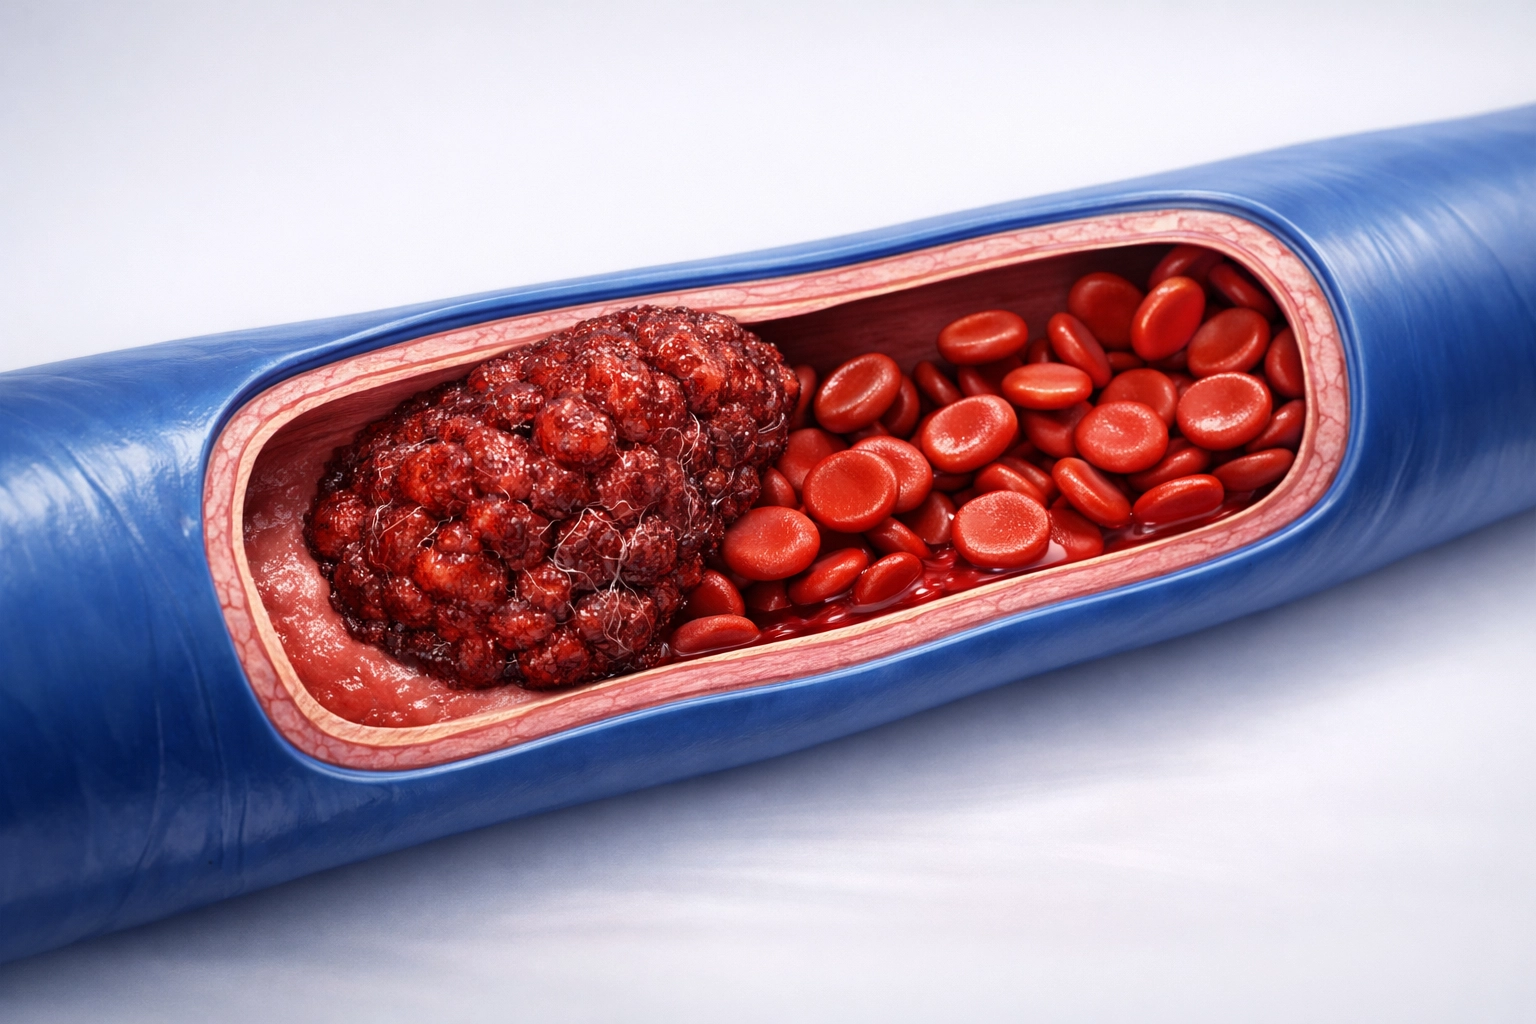

Derin ven trombozu, genellikle bacaklardaki derin toplardamarlarda kan pıhtısı oluşmasıyla ortaya çıkan ciddi bir dolaşım problemidir. Halk arasında “bacakta pıhtı oluşması” olarak da bilinen bu durum, kanın damar içinde pıhtılaşarak akışı kısmen ya da tamamen engellemesi sonucu gelişir. Bu tablo, tıbbi olarak bacak toplardamar tıkanıklığı şeklinde tanımlanır.

Normal şartlarda kan, toplardamarlar aracılığıyla kalbe doğru taşınır. Ancak çeşitli nedenlerle damar içinde pıhtı oluştuğunda kan akışı yavaşlar ya da durur. Bu durum yalnızca ilgili bölgede şişlik ve ağrıya yol açmakla kalmaz, aynı zamanda pıhtının yerinden koparak başka organlara gitme riskini de beraberinde getirir. Bu nedenle derin ven trombozu, erken tanı ve müdahale gerektiren bir hastalıktır.

Derin ven trombozu, damar içinde kanın pıhtılaşmasına yol açan çeşitli faktörlerin bir araya gelmesiyle ortaya çıkar. Temel olarak üç ana mekanizma bu süreci tetikler: kan akışının yavaşlaması, damar duvarının hasar görmesi ve kanın normalden daha kolay pıhtılaşması. Bu durumlar tek başına ya da birlikte geliştiğinde bacakta pıhtı oluşma riski artar.

Damar duvarının hasar görmesi de önemli bir etkendir. Travmalar, cerrahi işlemler veya bazı hastalıklar damar iç yüzeyinde hasara yol açabilir. Hasarlı damar yüzeyi, pıhtı oluşumunu kolaylaştırır. Aynı şekilde bazı kişilerde kanın pıhtılaşma eğilimi doğuştan daha yüksektir.